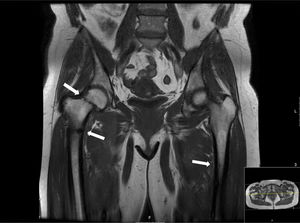

En el periodo de estudio se encontraron 2 casos de osteomalacia hipofosfatémica tumoral, lo que refleja una incidencia de 0,8 por cada 100.000 habitantes en 6 años, es decir, una incidencia anual acumulada de 0,13/100.00 habitantes. La media de edad de presentación fue de 53 años (49-57 años) y todos los casos fueron mujeres. Tanto el primer como el segundo caso comenzaron con dolores óseos, aunque posteriormente el primer caso presentó fractura de pie izquierdo, cadera derecha y diáfisis de ambos fémures (fig. 1). Los 2 casos presentaban hipofosfatemia y niveles elevados de FGF-23 al comienzo. El retraso promedio en el diagnóstico fue de 16 meses. En ambos casos los tumores fueron detectados en la exploración física y presentaron captación patológica en gammagrafía con receptores de somatostatina. En el primero de los casos el estudio se completó mediante tomografía axial computarizada facial y resonancia magnética nuclear cerebral. Ambos tumores se localizaron en partes blandas, el primero al nivel del maxilar superior derecho (con un diámetro de 2cm) y el segundo en la región pretibial izquierda (con un diámetro 0,8cm). El primer caso fue diagnosticado inicialmente de tumor desmoide, siendo posteriormente reclasificado como tumor fosfatúrico mesenquimal variante del tejido conectivo (PMTMCT). En el segundo caso las características anatomopatológicas se correspondieron con un angioleiomioma. Ambos pacientes recibieron inicialmente tratamiento con suplementos de calcio y vitamina D para posteriormente practicarle exéresis quirúrgica. Tras la cirugía se produjo normalización de los síntomas y de los niveles de FGF 23 ya a los 20 y 30 días, respectivamente. Ninguno de los pacientes presentó recidiva.